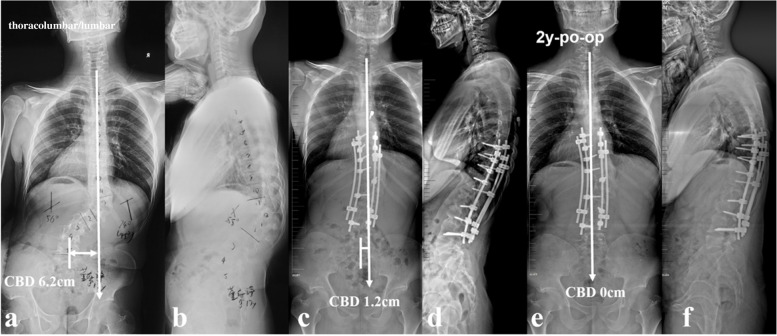

All the recruited patients were stratified according to the location of dystrophic curve apex: thoracic group, 4 cases (26.7%) (Fig. 1a, b); thoracolumbar/lumbar group, 11 cases (73.3%) (Fig. 1c, d). Among them, 1 patient in thoracic group and 3 patients in thoracolumbar/lumbar group received staged surgery with combined posterior-anterior or anterior- posterior approach (Table 1), while the rest 11 patients (73.3%) underwent posterior-only spinal instrumentation and fusion. Supplementary anterior fusion utilizing structural fibular allograft (2 patients) (Figs. 2, 8) or autogenous rib grafts (1 patient) (Fig. 3) was applied when the pedicle screw density in the apical region was distinctively low due to pedicle dystrophy disabling screw insertion. Stage 1 anterior release involving intervertebral disc resection and autogenous rib grafting was performed in 1 patient of thoracolumbar/lumbar group, followed by skull-femoral traction for 2 weeks and subsequent stage 2 posterior spinal correction and fusion.

The pre-op, post-op and final Cobb angle of main curve, kyphosis and CBD for thoracic and thoracolumbar/lumbar groups were shown in Table 2. The incidence of CCI immediately after surgery was 0.0 and 63.6% for thoracic and thoracolumbar/lumbar groups, respectively. Both Cobb angle of main curve and regional kyphosis were significantly corrected and well-maintained during follow-up (Table 2). The post-op CBD in thoracolumbar/lumbar group didn’t improve significantly (39.6 ± 12.5 mm vs. 33.6 ± 18.7 mm, p = 0.380). However, this post-op CBD got compensated spontaneously during follow-up (33.6 ± 18.7 mm vs. 8.3 ± 11.3 mm, p = 0.002).

The present study represented a homogeneous case series of dystrophic NF1 patients with convex trunk shift, and the incidence reached 8.4%. The stratification of distinguishing thoracic from thoracolumbar/lumbar CCI was important, as the incidence of immediate post-op CCI (≥3 cm) was 0.0 and 63.6% for thoracic and thoracolumbar/lumbar groups, respectively. This separation was essential because of its quite different prognosis. The likely mechanism was that the thoracic CCI was usually associated with sufficient distal non-dystrophic pedicles and reliable distal screw purchases to achieve sufficient correction of distal fractional curve and subsequently a horizontal takeoff (Fig. 5). For thoracolumbar/lumbar CCI, limited and unreliable distal screw purchases were inclined to achieve poor correction of lumbosacral fractional curve and subsequently leave residual takeoff angle, increasing the risk of failure of coronal rebalance (Fig. 6).

The follow-up data revealed that patients in the imbalanced group experienced spontaneous improvement of CCI over time (Ratio of CBD < 3 cm: 100%). This usually resulted in an acceptable but not satisfying coronal alignment because residual tilting of the instrumentation mass and/or junctional angulation centering around LIV existed (Fig. 8), and might result in implant failure (Fig. 5). Both distal compensation (decreased tilting of the instrumentation mass and LIV to the convex side) and proximal compensation (increased UIV disc angle) accounted for such coronal rebalance, and our data was suggestive that the distal compensation was the mainstay compensative mechanism. This was in line with Bao’s previous finding that LIV at L4 or higher was correlated to a higher chance of spontaneous coronal rebalance [ref. 7].